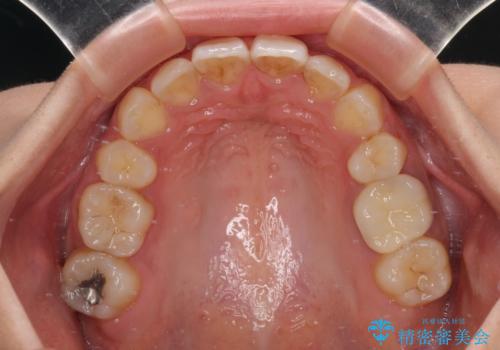

デコボコと口元の突出感 ハーフリンガルでの抜歯矯正

- 前歯のデコボコと上顎の前突感による口の閉じにくさを気にして来院された患者様です。

目立たない装置を希望されたので、上顎が裏側装置のハーフリンガルを選択し、上下左右の小臼歯(計4歯)を抜歯して矯正治療を行うこととしました。

表側のワイヤー矯正に比べると治療期間は長く、費用も高額となりますが、どうしても目立たせたくないという方にはお勧めの抜歯矯正です。